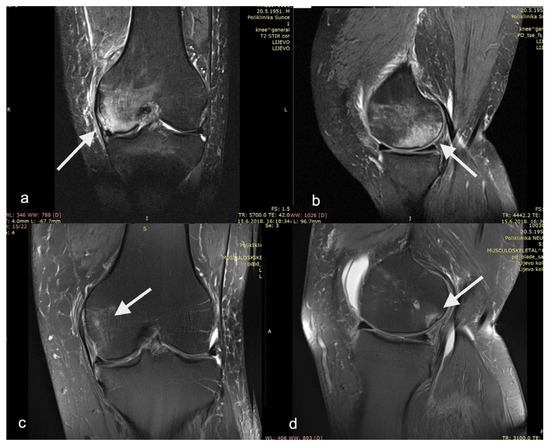

| Presence of hypercaptating lesion (>2 cm in diameter) in T2-weighted fat suppression images located in the subchondral region of the tibial or femoral condyle | Tricompartmental OA of the affected knee |